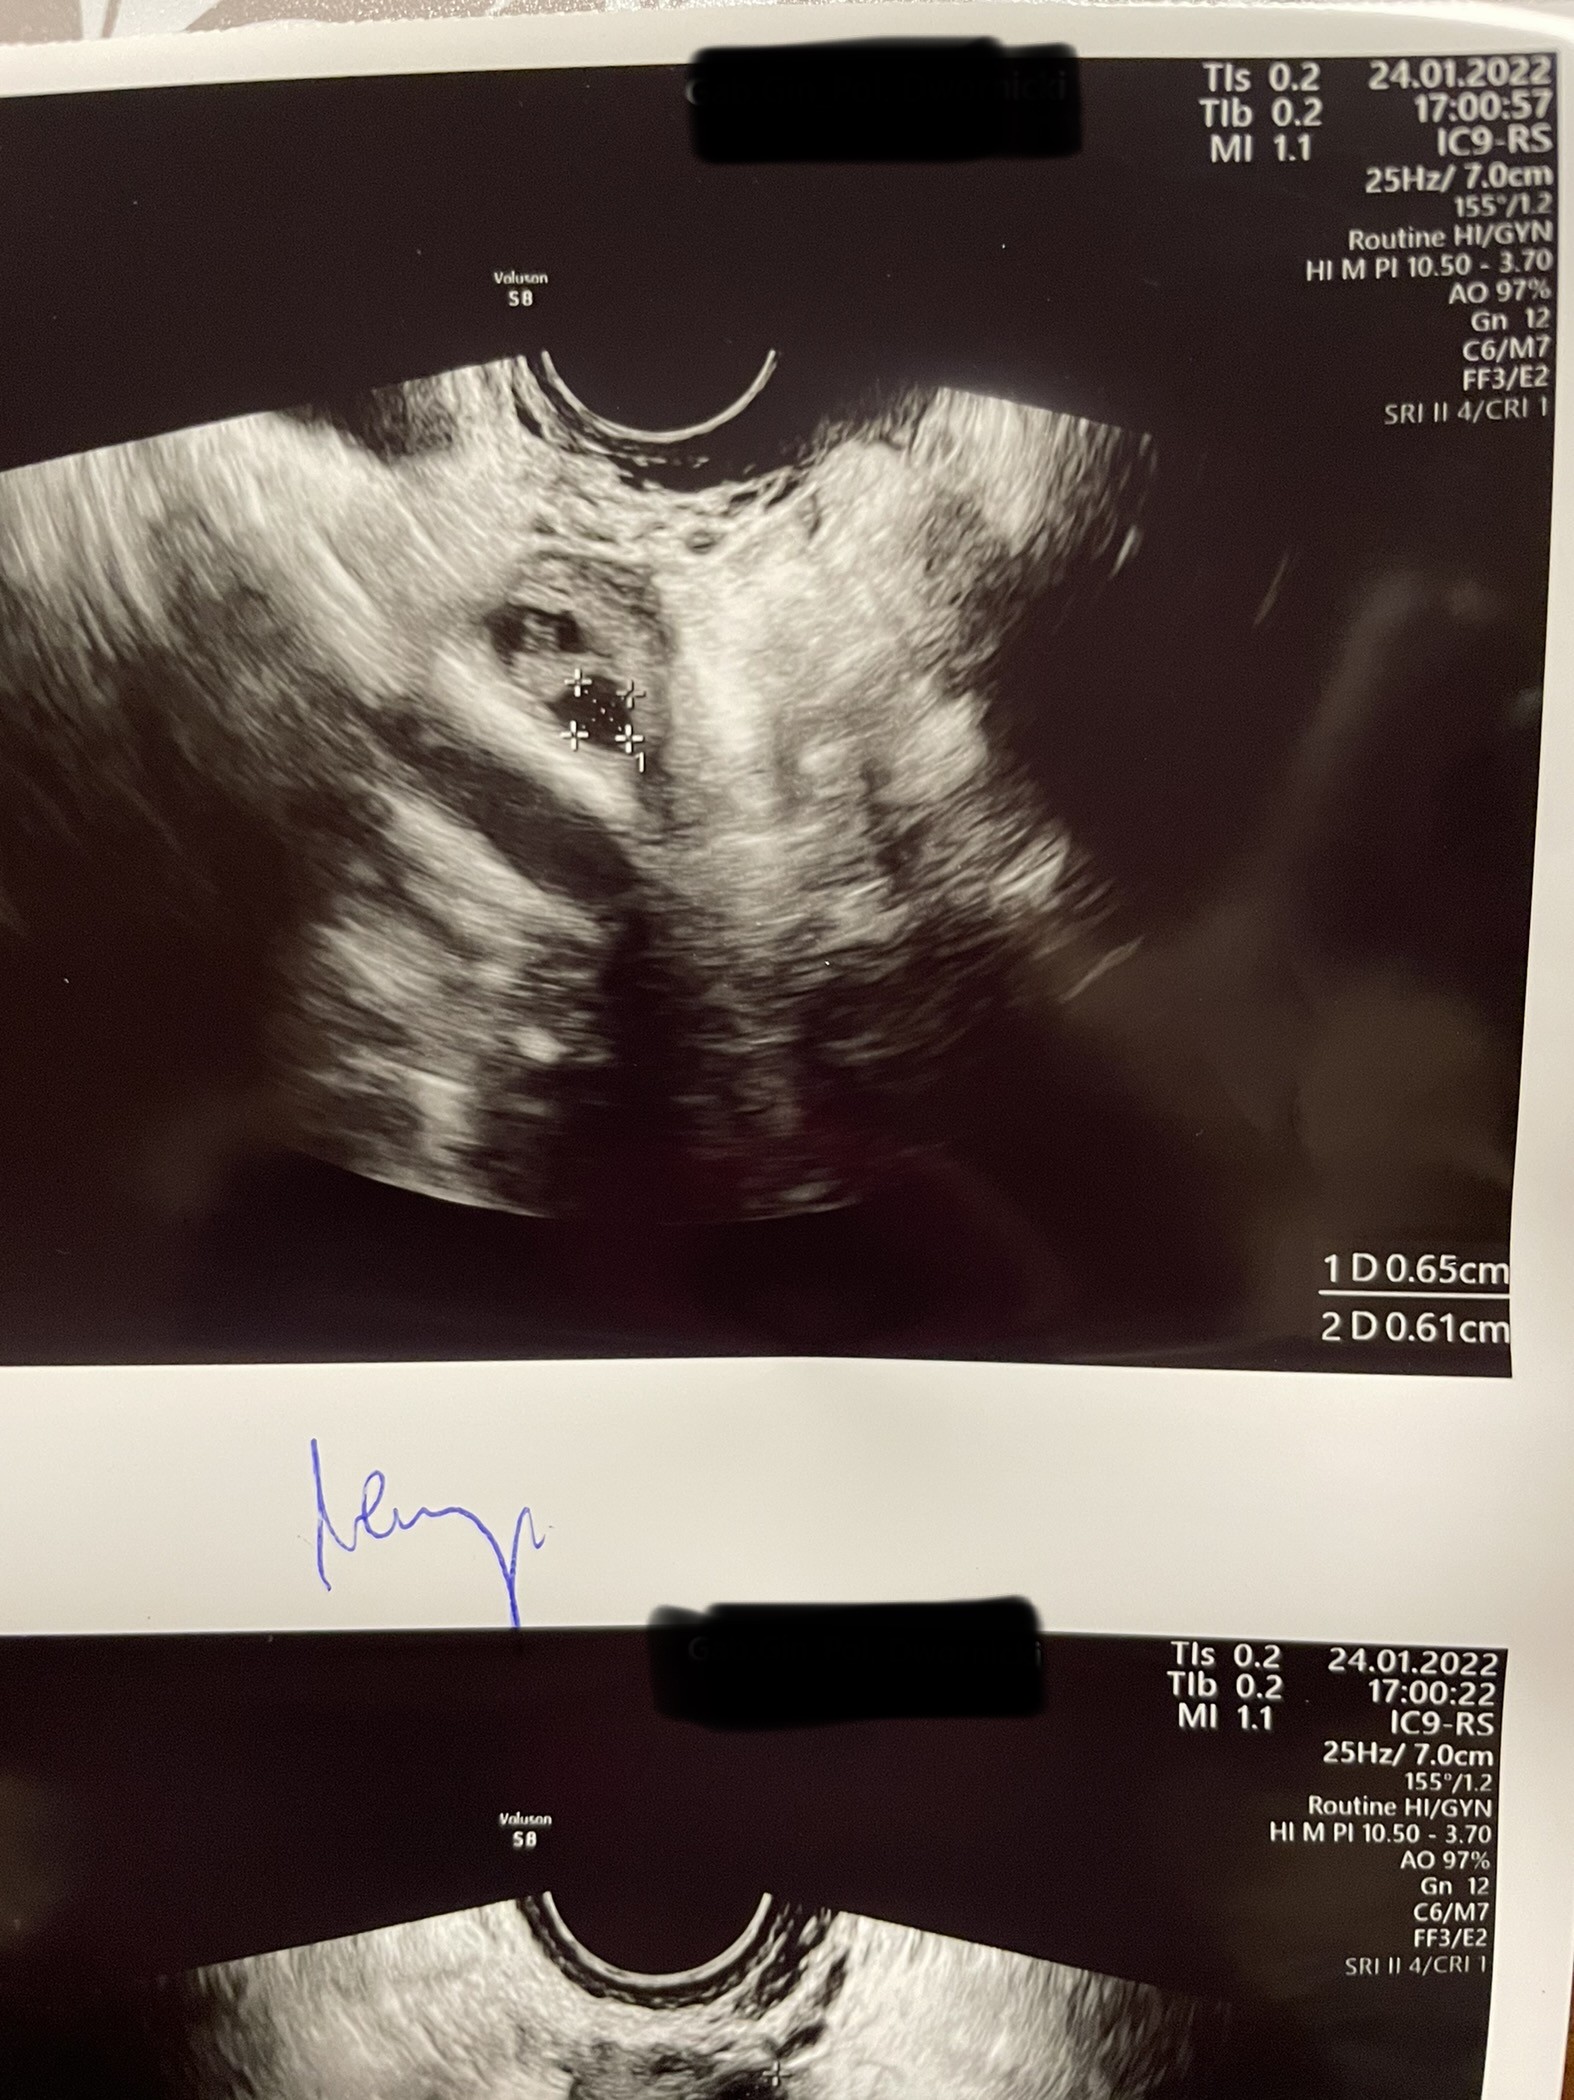

Hej, już po wizycie a wiec

Jajnik lewy

Pęcherzyk pierwszy 0.61cm

Pęcherzyk drugi 0.65cm

Jajnik prawy pęcherzyk 0.86cm

Endomedrium 0.72cm

Dziś 7DC następna wizyta w czwartek

Czekaj… ta są wszystkie pecherzyki poniżej 10mm, więc ich w ogóle powinno być więcej (nawet kilkanaście) w każdym jajniku, to nie są pecherzyki dominujące. Chyba, ze 1,61, 1,65 i1,86?

Pęcherzyk dominujący mam w prawym jajniku. W lewym mam 2 tylko (aż). Dopiero rosną, w czwartek zobaczymy jak duże będą.